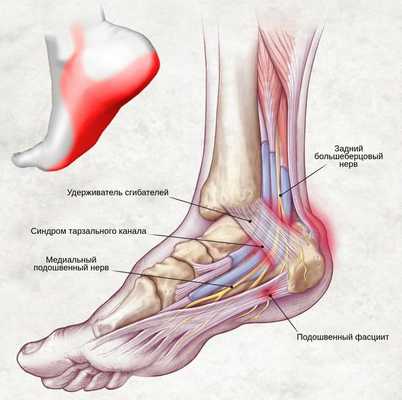

Синдром тарзального канала - симптомы и лечение

Синдром тарзального (предплюсневого) канала — это периферическая мононевропатия нижней конечности, которая возникает в результате сдавления большеберцового нерва, проявляющаяся болью в области голеностопного сустава по внутренней стороне стопы.

Существует ряд других названий этой патологии: синдром ущемления большеберцового нерва, синдром канала Рише, синдром предплюсневого канала. [9]

Одной из ветвей периферической нервной системы является большеберцовый нерв. Он начинается в пояснично-крестцовом сплетении спинномозговых корешков, проходит посередине вниз к подколенной ямке латеральнее (как бы в стороне) и поверхностнее подколенных сосудов. [4] Затем нерв спускается между обеими головками икроножной мышцы, проникает под сухожильную дугу камболовидной мышцы, после чего спускается между последней и глубокой мышцами к медиальной лодыжке голени.

На уровне голеностопного сустава большеберцовый нерв проходит через жёсткий остеофиброзный туннель — тарзальный канал. [1] Это пространство спереди ограничено большеберцовой костью, а снаружи — задним отростком таранной кости и пяточной костью, а также удерживателем сгибателей (сухожилий).

Канал делиться на два этажа:

- верхний (залодыжечный);

- нижний (подлодыжечный).

Анатомически в канале сосуществуют несколько сухожилий мышц: задняя большеберцовая, сгибатель большого пальца и длинный сгибатель пальцев. [8] [9] Причём короткий и длинный сгибатели большого пальца стопы являются основными мышцами, которые получают иннервацию после выхода нерва из канала предплюсны.

Ишемическая компрессия содержимого тарзального канала приводит к изменению кровообращения в стопе и слабости короткого сгибателя большого пальца стопы. Хроническое сдавление в результате нарушения той же иннервации способствует деформации по типу молоткообразных (кошачьих) пальцев. Также отмечается, что патология сопутствует почти каждому случаю вальгусной деформации стопы.